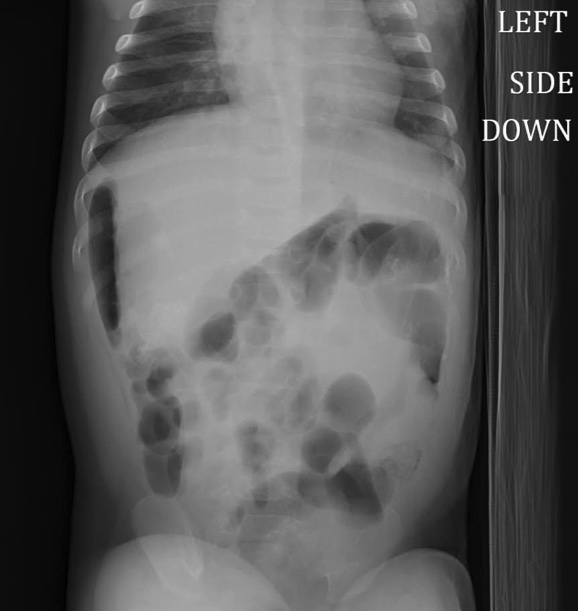

A 3 month old male with a history of ileostomy s/p revision, left inguinal hernia s/p repair, and incisional hernia presents to the ED with abdominal distension and vomiting. He is febrile and irritable. A plain abdominal xray is shown below. What's the diagnosis? Scroll down for answer.

Answer: Perforated viscus

- X-ray shows intraperitoneal free air - this case demonstrates the the importance of 2 views as free air notable tracking on the right side of abdomen with left side is down

- Management involves stat surgical consultation, broad spectrum antibiotics including anaerobic coverage, and fluid resuscitation